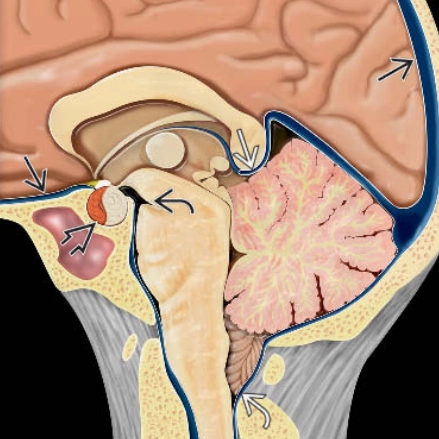

• Thoát vị não (Brain herniation)

• Thoát vị móc hải mã (Uncal Herniation)- Thoát vị xuyên lều xuống dưới một bên (Unilateral Descending Transtentorial Herniation)

• Thoát vị trung tâm (Central Herniation)-Thoát vị xuyên lều xuống dưới hai bên (Bilateral Descending Transtentorial Herniation)

• Thoát vị lều tiểu não hướng lên (Ascending Transtentorial Herniation)

• Thoát vị hạnh nhân tiểu não (Tonsillar Herniation)